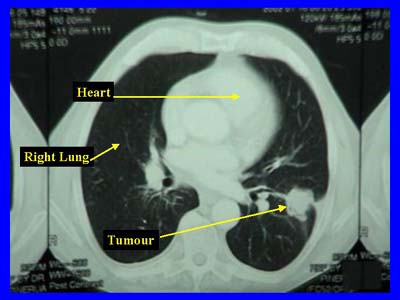

Weniger Tote durch Lungenkrebs dank CT-Screenings